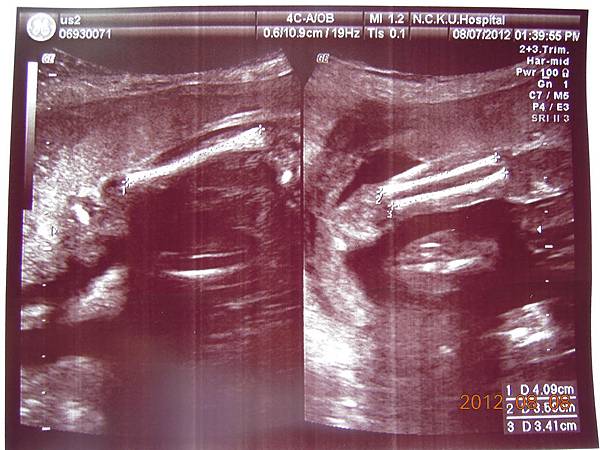

可以看到的是在逼逼的上方剛好被胎盤擋著,比較看不到他的正面,除了肛門無法看到(怕沒有肛門),醫師說現在看不到,小雞雞也沒照他的大小(我怕他發育不良),其他身體器官包括腦部剖有量測他的大小及羊水多寡(我怕像上次一樣羊水太少),今天量出來是12,喔彌陀佛~~

大約檢查了有四五十分鐘,也數了他的手指腳趾,看起來是沒異狀,就叫我等下把報告拿過去門診給游醫師看,還給我ㄧ堆照片,就是下面那些~~

接下來就是他的一堆檢查照片啦~~